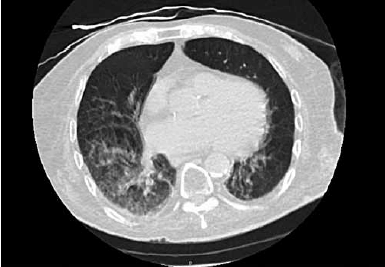

Paciente de 90 anos e admitido no pronto-socorro com história de 1 dia de evolução de tosse, sonolência e diminuição da ingestão de alimentos. Foi realizada uma tomografia computadorizada de tórax, apresentada a seguir:

(Arquivo pessoal; imagem usada com autorização)

Em relação ao caso, assinale a alternativa correta.